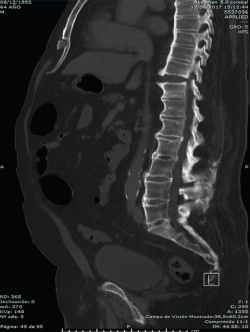

En la Figura 3 puede verse un corte sagital de la TAC cervical con sindesmofitosis también a este nivel, provocando un verdadero canal estrecho cervical en el raquis cervical alto.

Figura 3. Corte sagital de tomografía axial computarizada cervical.